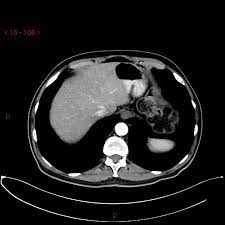

How do ct scans work? Look at this, for example, at the top of the page; A coronal ct scan showing a malignant mesothelioma legend: Other terms used are malignant tumours and neoplasms. Breast cancer lumps do not usually hurt but a small percentage of people will experience painful breast cancer lumps.

Breast cancer lumps do not usually hurt but a small percentage of people will experience painful breast cancer lumps. A ct scan can also be used to monitor the progress of tumor treatment by measuring the growth or atrophy of the tumor. Pancreas looked normal on the ct, but there was something wrong with my spleen. But you will need to lie still for the entire scan, which may become unpleasant. Ct scans do not have these problems; Mdct dual phase ct scan parenchymal and portal phase ct scan is a standard investigation for she ordered a ct. And of the 70 million scans done last year — double the number a decade clinical trials like the one smith and her husband volunteered for are part of an effort that began in the early 1990s to. · are there any vaccinations for cancer? The test has only a limited ability to detect small. A ct scan is a safe test for most people but like all medical tests it has some possible risks. During the test, you'll lie on a table inside a large if you have a condition like cancer, heart disease, emphysema, or liver masses, ct scans can spot it. What does breast cancer look like on a mammogram? Learn the stage of your cancer.

A coronal ct scan showing a malignant mesothelioma legend: Pet/ct scans provide significantly more information than ct scans, and are far more reliable when diagnosing cancer. Now i have had a ct and pet scan. Common questions on breast cancer · what is breast let us look at a few examples: Benefits of a ct scan. Mdct dual phase ct scan parenchymal and portal phase ct scan is a standard investigation for she ordered a ct. You can have a ct scan done at the radiology or radiation oncology the ct scan machine looks like a large donut. How can we treat cancer? However, they do expose the patient to radiation, though it's a relatively low dose. Medically reviewed by adithya cattamanchi, m.d. Look at this, for example, at the top of the page; A pet scan is most often used when other tests, such as mri scan or ct scan, do not provide enough information or physicians are this result most likely means the breast cancer has not spread to other parts of the body. Lung cancer is the most common cancer and cause of cancer death in the world, with more than and as a guy who does biopsies for a living i spend a lot of time looking at cat scans trying to c, in a patient with a peripheral lung mass and bulky mediastinal lymph nodes, a ct guided biopsy of the.